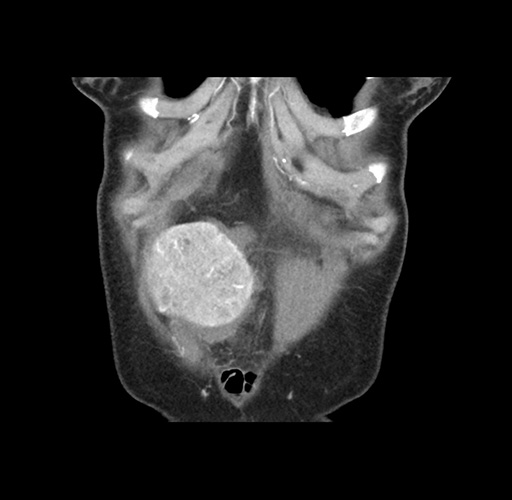

Imaging Analysis

Look through the patient's CT scan to identify any areas of concern for the necessary procedure.

Based on your CT findings, which issue(s) would give reason for "planned slowing down moment(s)" in this case?

Considering a standard left lateral sectionectomy procedure, what step(s) of the operation would you do differently in this case ?